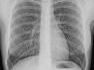

Der südostösterreichische Lungentag wandert in den Westen nach Bregenz ins Theater am Kornmarktplatz. Am 2.Oktober von 14:00-18:00 Uhr ist die Bevölkerung herzlich dazu eingeladen sich über Asthma Brochiale, diverse Allergien, COPD, Schnarchen und Schlafapnoe, Raucherentwöhnung, Lungenkrebs, etc. zu informieren.

Mit einem kostenlosen Lungenfunktionstest kann festgestellt werden wie fit ihre Lunge ist. Der Test selbst dauert rund 10 Minuten. Dabei bläst der zu Testende über ein Mundstück in einen sogenannten Spirometer. Dieser misst, wie viel Luft die Lunge nach einer maximalen Einatmung enthält, und die Geschwindigkeit, mit der Luft aus der Lunge ausgeatmet werden kann. Durch die so ermittelten Werte können Lungenfachärzte bereits in einem sehr frühen Stadium mögliche Erkrankungen der Lunge feststellen.